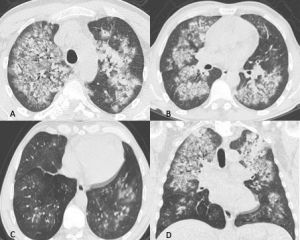

Figura 13: Uomo di 45 anni giunge in Pronto Soccorso per IRA e grave anemizzazione. La TCAR eseguita all’ingresso (scansioni assiali A-B-C e ricostruzione MPR sul piano coronale D) mostra la presenza in entrambi i polmoni di multiple aree di aumentata densità con aspetto in parte a "vetro smerigliato" ed in parte consolidativo con broncogramma aereo nel contesto e distribuzione simmetrica, prevalente in sede perilare con risparmio delle zone subpleuriche. In considerazione della clinica e della distribuzione delle lesioni l’ipotesi diagnostica formulata (in seguito confermata dal BAL) è quella di emorragia alveolare diffusa.

Figura 14: Paziente di sesso femminile, 75 anni, con storia di interstiziopatia polmonare inquadrata come UIP probabile dal 2018. La paziente giunge al Pronto Soccorso per repentino e grave peggioramento della funzionalità respiratoria. Le immagini TCAR assiali (A-B) documentano la presenza in entrambi i polmoni di multiple aree a “vetro smerigliato” con distribuzione diffusa. Dopo aver escluso le ipotesi di edema cardiogeno e di infezione polmonare viene posta diagnosi di esacerbazione di fibrosi polmonare idiopatica.

In TCAR inizialmente si documenta “vetro smerigliato” diffuso, dopo due o tre giorni si sovrappone ispessimento liscio dei setti inter ed intralobulari (crazy paving) ed in seguito si riduce il “vetro smerigliato” e compaiono noduli centrolobulari e consolidazione. La tipica distribuzione simmetrica e peri ilare con risparmio delle zone sub pleuriche e prevalente nei lobi inferiori (Figura 13) oltre che la clinica consente di porre diagnosi differenziale con la polmonite da SARS-CoV-2.

In TCAR l’EA è caratterizzata dalla comparsa di aree a “vetro smerigliato” che si sovrappongono alle alterazioni fibrotiche (Figura 14).

In letteratura sono stati descritti tre pattern principali di EA: periferico, multifocale e diffuso. Nel pattern periferico le aree di aumentata densità si riconoscono nella parte interna della zona periferica adiacenti all’honeycombing subpleurico. Il pattern multifocale è caratterizzato dalla presenza di aree di aumentata densità nelle zone centrali e periferiche, tuttavia, l’interessamento parenchimale ha estensione limitata ed interessa solo alcune zone di polmone. Nel pattern diffuso si osserva aumento della densità del parenchima polmonare esteso sia alle zone periferiche che in quelle centrali. La distinzione di questi tre pattern è clinicamente molto importante; infatti, il pattern diffuso è quello caratterizzato da una prognosi peggiore.